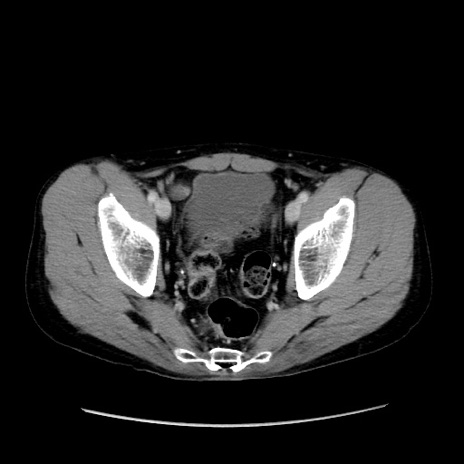

症例37(横断像)

【症例】40歳代 男性

【主訴】腹痛

【現病歴】4時間ほど前に電車に乗車中に臍部上より腹痛出現。徐々に増悪し起立困難となり、救急外来受診。生ものは数日食べていない。今朝お雑煮を食べた。

【身体所見】BT 36.8℃、BP 117/84mmHg、HR 91/min、SpO2 97%、苦悶様、腹部:臍上部広範囲圧痛あり、反跳痛±

【データ】WBC 8100、CRP 0.03